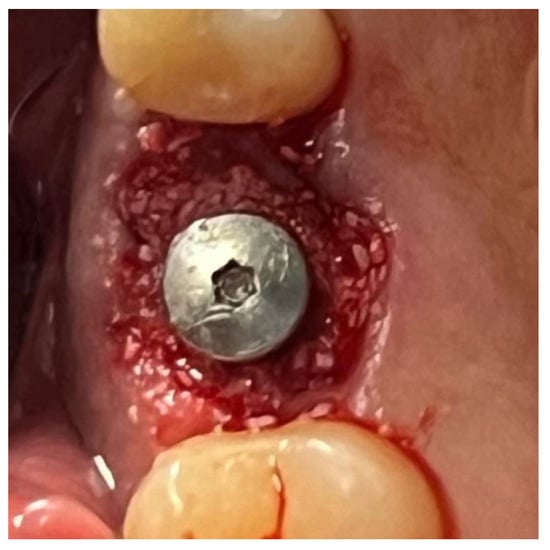

In a 49-year-old patient with ischemic heart disease, Glubran II was used as a stabilizing material for natural bone graft granules at a site rehabilitated with implant-prosthetic treatment, with the aim of achieving volumetric enhancement of the buccal bone. Following specific guidelines for surgical treatment of ischemic heart disease (4), implant therapy was carried out (Figure 8). Natural bone graft material (Bio-Oss®—Geistlich, Baden-Baden, Germany) was applied and stabilized with Glubran II. The application was made using an endodontic needle, depositing single droplets of the glue to cover the entire graft material before placing the prepared flap on top (Figure 9). This technique achieved stable graft fixation at the recipient site, demonstrating the efficacy of Glubran II for internal use (Figure 10).

During the postoperative period, no complications were reported, and no signs of material rejection or inflammation at the surgical site occurred. The site was sutured with absorbable sutures (Ethicon Vicryl Rapid 4/0, Johnson & Johnson, New Brunswick, NJ, USA), and soft tissue healing was completed within 15–20 days. A proper evaluation of graft integration and potential bone regeneration will require 3–4 months, but the current results show Glubran II’s effectiveness in stabilizing the graft and preventing inflammation, both in the bone and soft tissue, making it a valuable tool for socket preservation techniques.

Figure 10. Surgical site at the end of the polymerization time of Glubran II; the site was subjected to tensile testing, with positive results under the applied tensions.